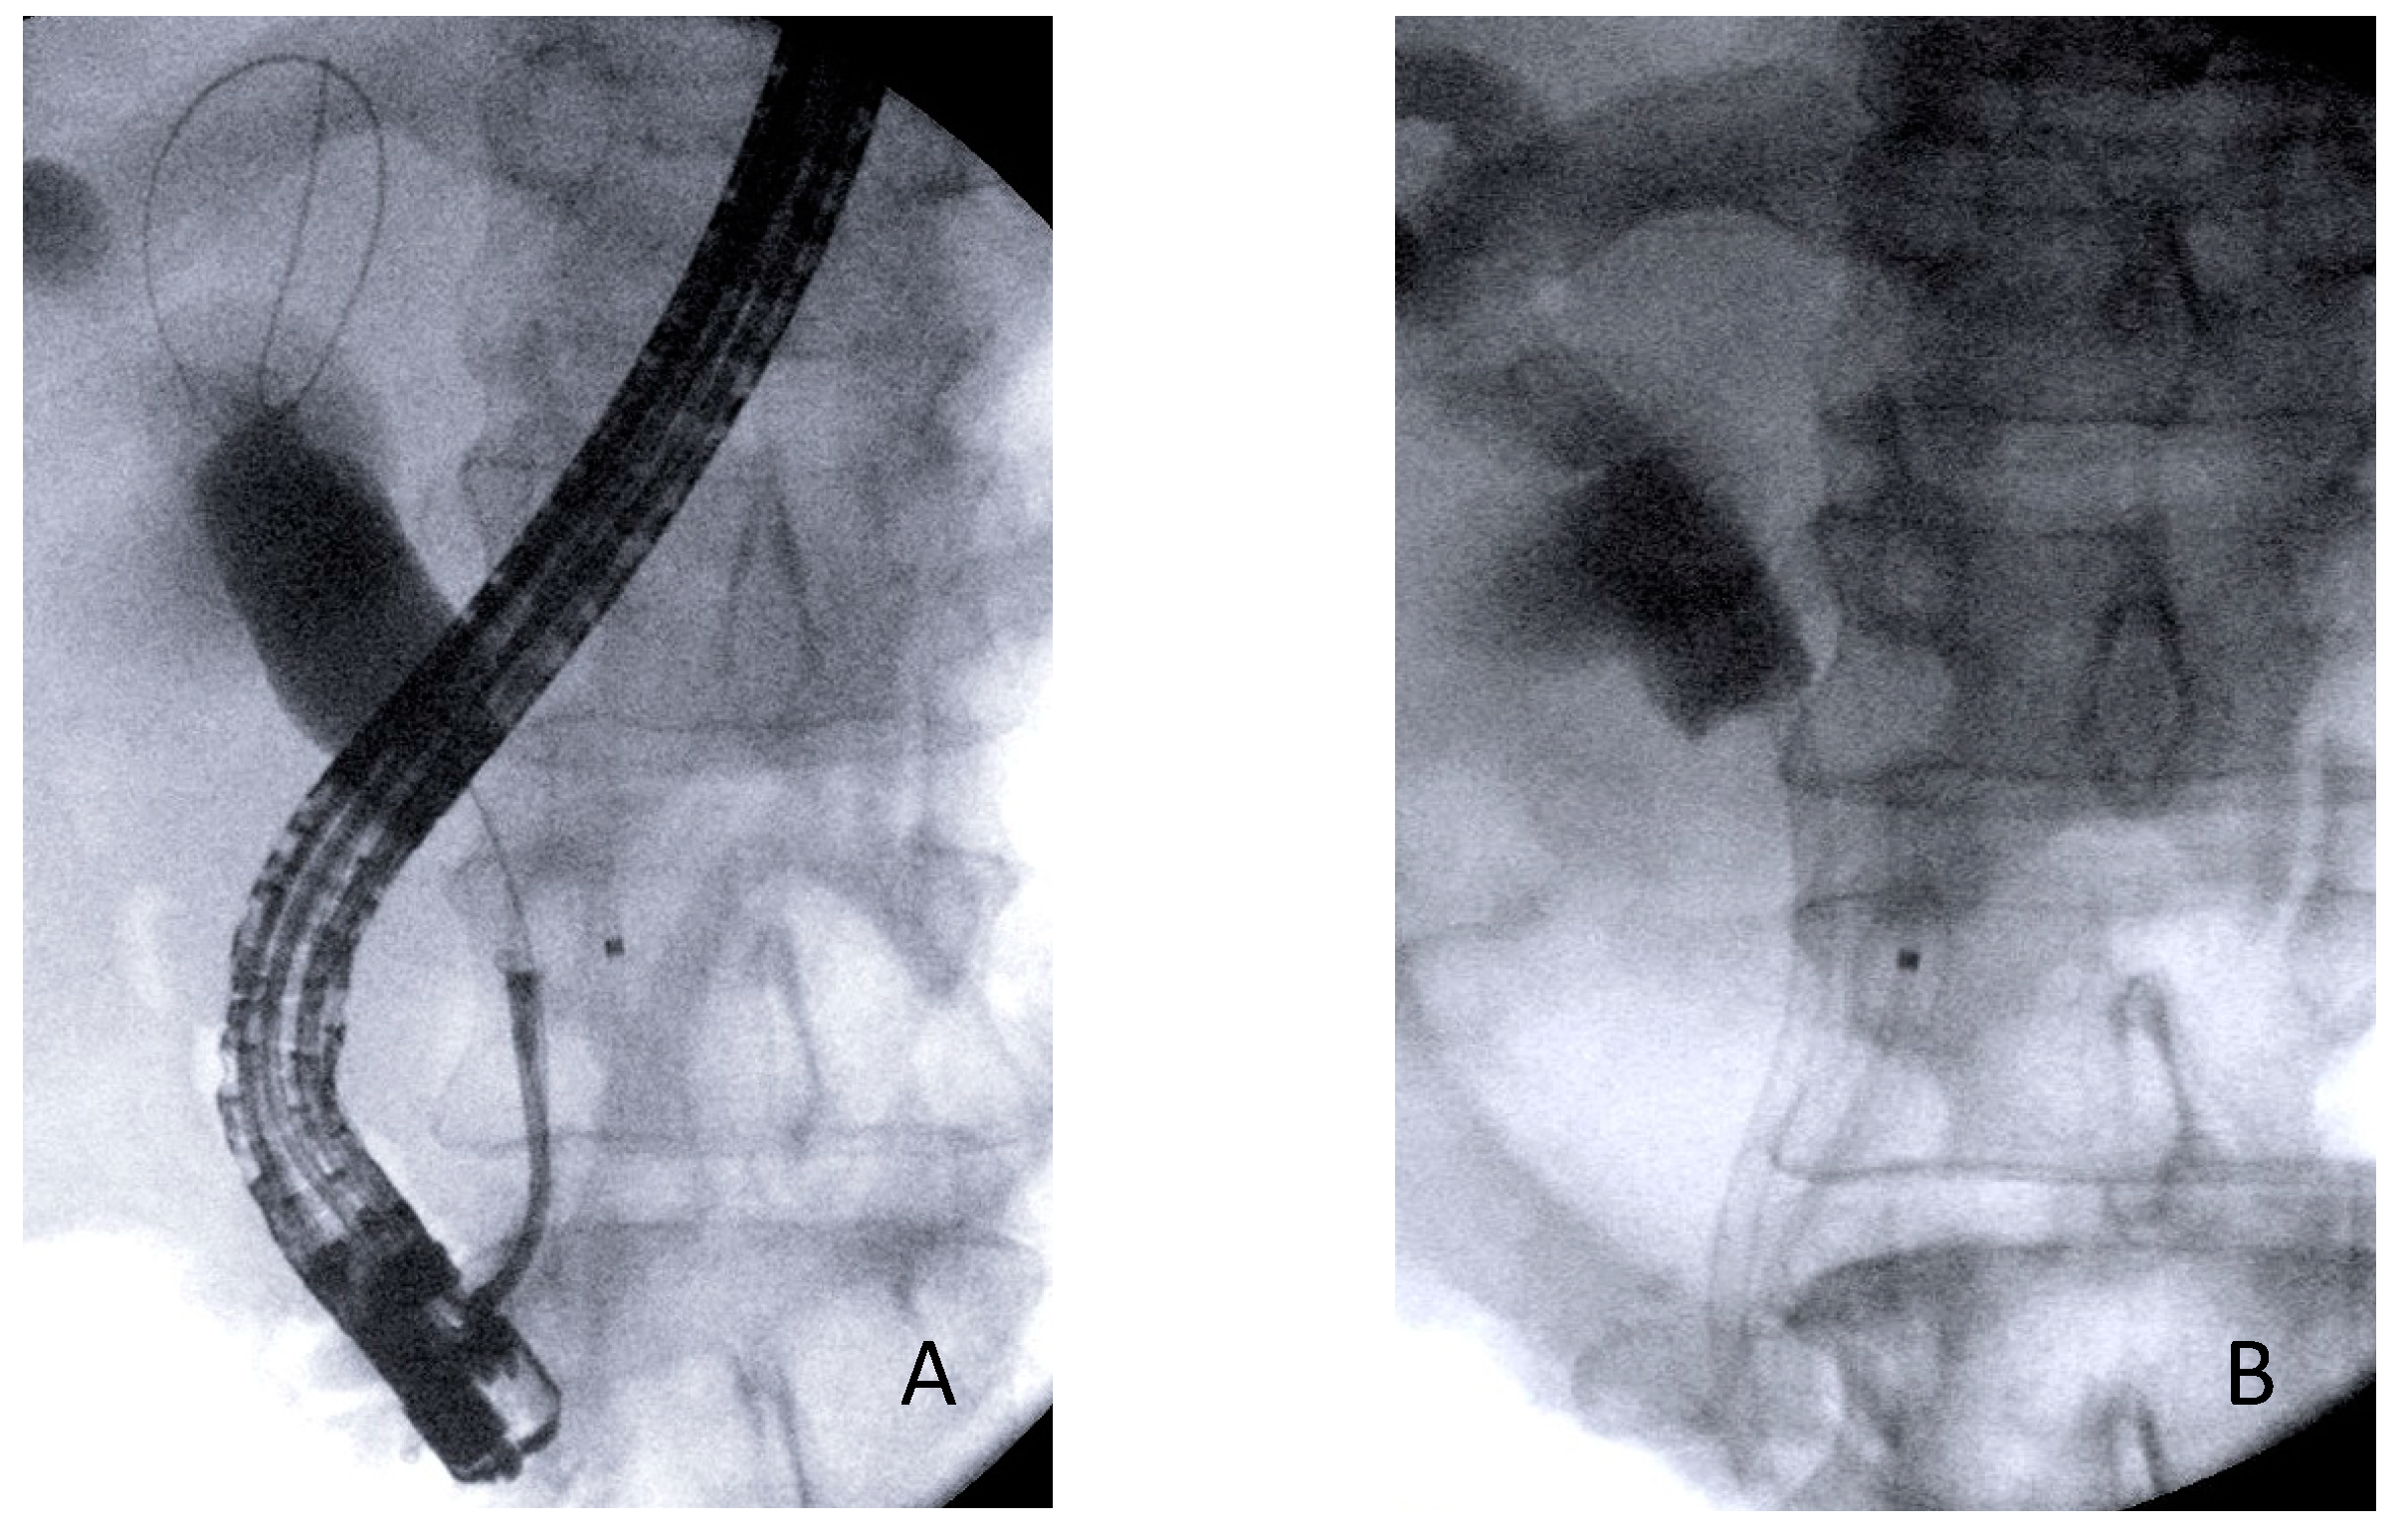

2.1. Patient Selection and Endoscopic Procedures